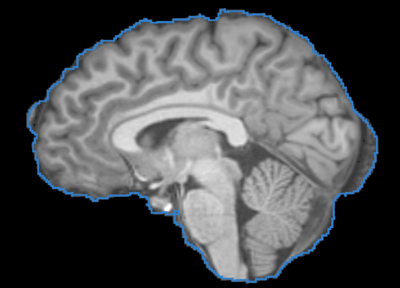

Image:T1_BET_BVeR.png|The BVeR application showing segmentation outlier corrections (brain external frontier)

This is a CLI module for Brain Volume Refinement (BVeR) tool, which is useful to correct brain segmentation errors that may appear in commonly brain extraction methods. The BVeR algorithm was extensively tested on structural MRI images (T1 and T2) of normal individuals. Further details are found at PAPER

• It is frequent to appear segmentation errors (outliers) in commonly used brain extraction algorithms (BET, FreeSufer, BSE, AFNI, ROBEX, etc), thus the BVeR application can be helpful.

• Due to decrease of segmentation errors, the outcome of large-scale morphological measurements can have better precision (e.g. cortical thickness and brain atrophy)